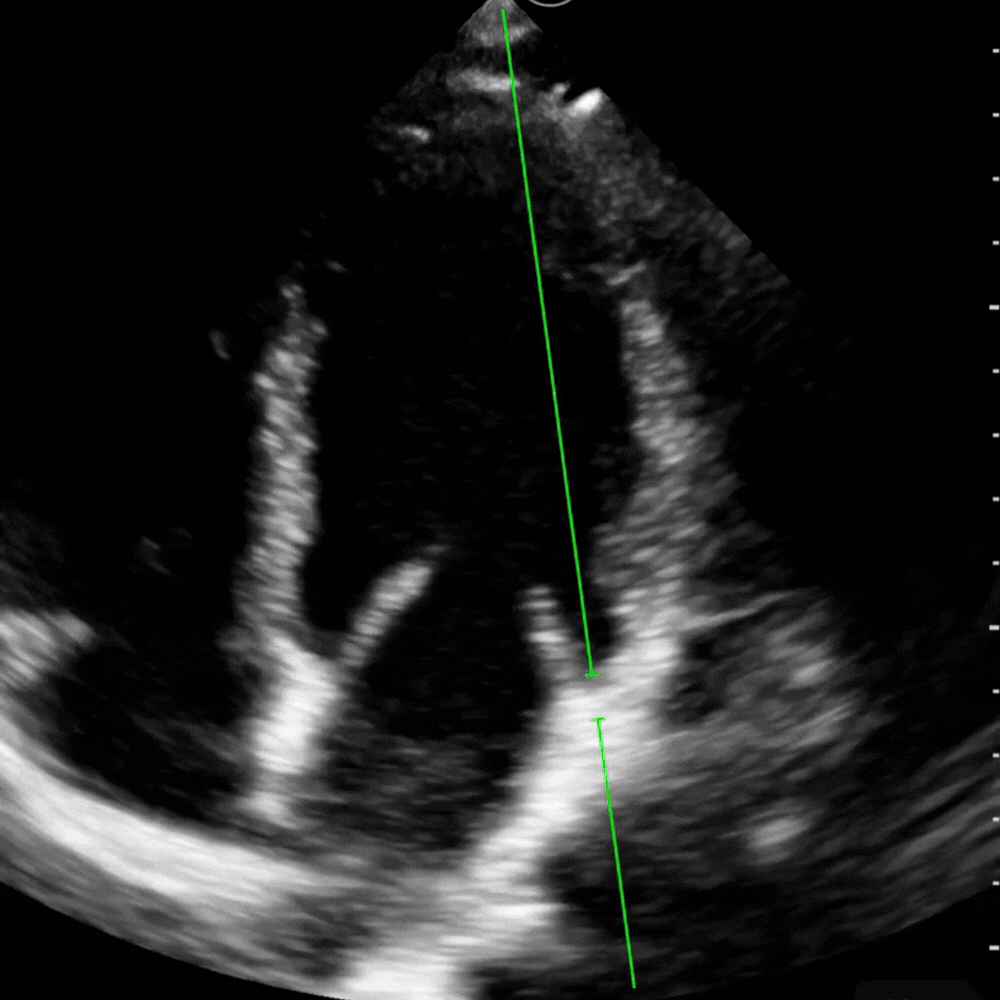

Parasternal grand axe → E point-septal separation (EPSS)

Méthode simple pour estimer la fonction systolique du VG. En parasternale grand axe, on place le curseur en mode M sur l’extrémité du feuillet antérieur mitral et le septum. On mesure la distance entre la valve en position ouverte maximale et le septum.

Valeur normale : 0–6 mm.

Zone grise : 6–7 mm.

Pathologique : > 7 mm, généralement associé à une FEVG < 50 %.

EPSS très élevée : > 10 mm, suggère une dysfonction sévère du VG.